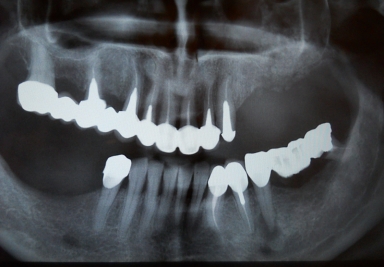

Dental implants premolar

Dental implants upper second premolar, upper second molar

External sinus lifting

Sinus lifting on the left side of the maxilary